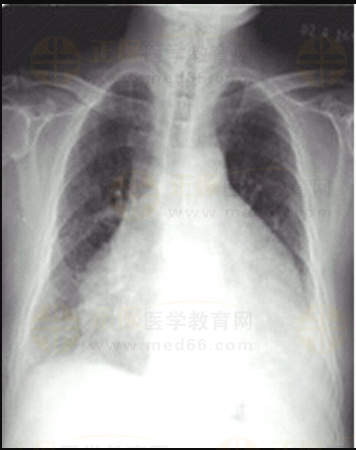

03卷-5.女性,63歲,咳嗽、咳痰、胸悶2月,伴下肢浮腫4天。診斷

A.靴形心

B.正常心臟

C.普大型心臟

D.梨形心

【該題針對(duì)“ X線-心臟增大(二尖瓣型、主動(dòng)脈型和普大型) ”知識(shí)點(diǎn)進(jìn)行考核】